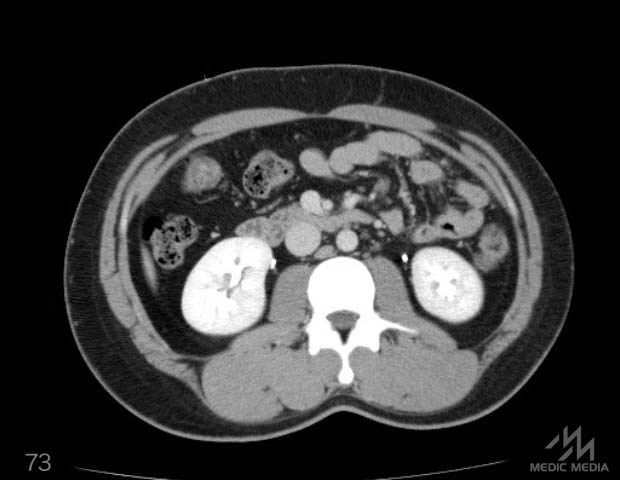

造影CT

消化器

肝区域